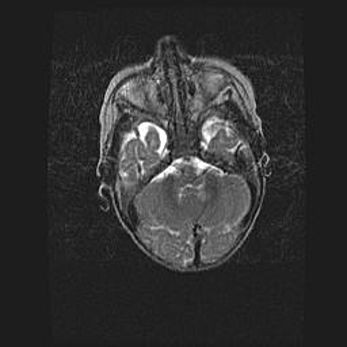

Мальформация Денди-Уокера. Киста задней черепной ямки.

Агенезия мозолистого тела.

Возраст: 2,5 месяца

Вес: 2420 г

Пол: женский

Окружность головы: 37 см

Срок гестации: 32 недели

Мальформация Денди—Уокера — редкий вид патологии ЦНС, представляющий собой врожденный порок развития каудального отдела ствола и червя мозжечка, ведущий к неполному раскрытию срединной (Мажанди) и латеральных (Лушка) апертур IV желудочка мозга. Для этогно синдрома характерна триада симптомов: гипотрофия червя мозжечка и/или полушарий мозжечка, кисты задней черепной ямки, гидроцефалия различной степени. В 70% случаев порок сочетается и с другими аномалиями головного мозга, в частности с агенезией мозолистого тела.